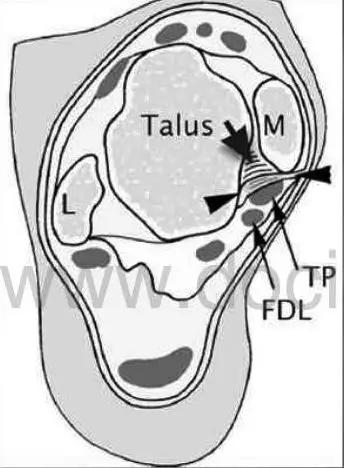

影像学表现为距骨胫骨间肌腱及趾长屈肌腱水肿、增厚,内踝及距骨后内侧骨赘形成。

轴位示意图示后内侧撞击综合征:M:内踝;L:外踝;TP:胫后肌腱;FDL:趾长屈肌腱;Talus:距骨。短箭:距骨胫骨间肌腱深层纤维;箭头:距骨胫骨间肌腱后部纤维。

X线平片示胫骨后部骨赘形成,MR质子像黑箭示胫骨内后侧骨赘形成,白箭示内后侧软组织增厚, 白箭头:胫后肌腱;黑箭头:趾长屈肌腱